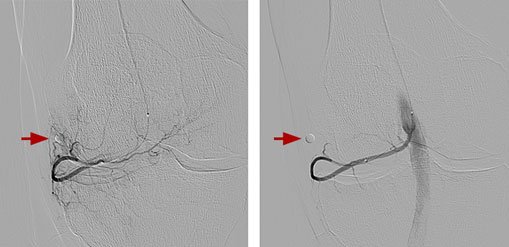

(Initial (left) and final (right) angiograms of the knee after embolization. A circular marker was placed at the site of pain. The reduced blood-flow at the site of pain after embolization reduced inflammation of the knees)

Genicular artery embolization (GAE) is performed with moderate ‘twilight’ sedation as an outpatient procedure, meaning the patient will go home after the procedure. The procedure generally takes one to two hours. Our IR physicians will insert a small catheter (a thin hollow tube) into the artery of the patient’s upper thigh and, with the use of X-rays, guide the catheter to the arteries supplying the lining of the knee. Tiny particles are then injected through the catheter into these arteries, reducing the blood supply. This in turn reduces the inflammation associated with osteoarthritis, which alleviates the Pain.